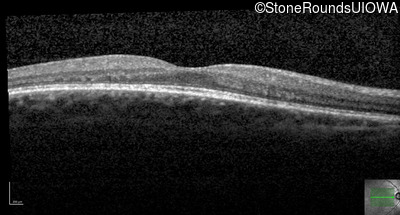

Optical Coherence Tomography - Left - 20/20 -1

Exemplar / OCT Stack

OCT Stack